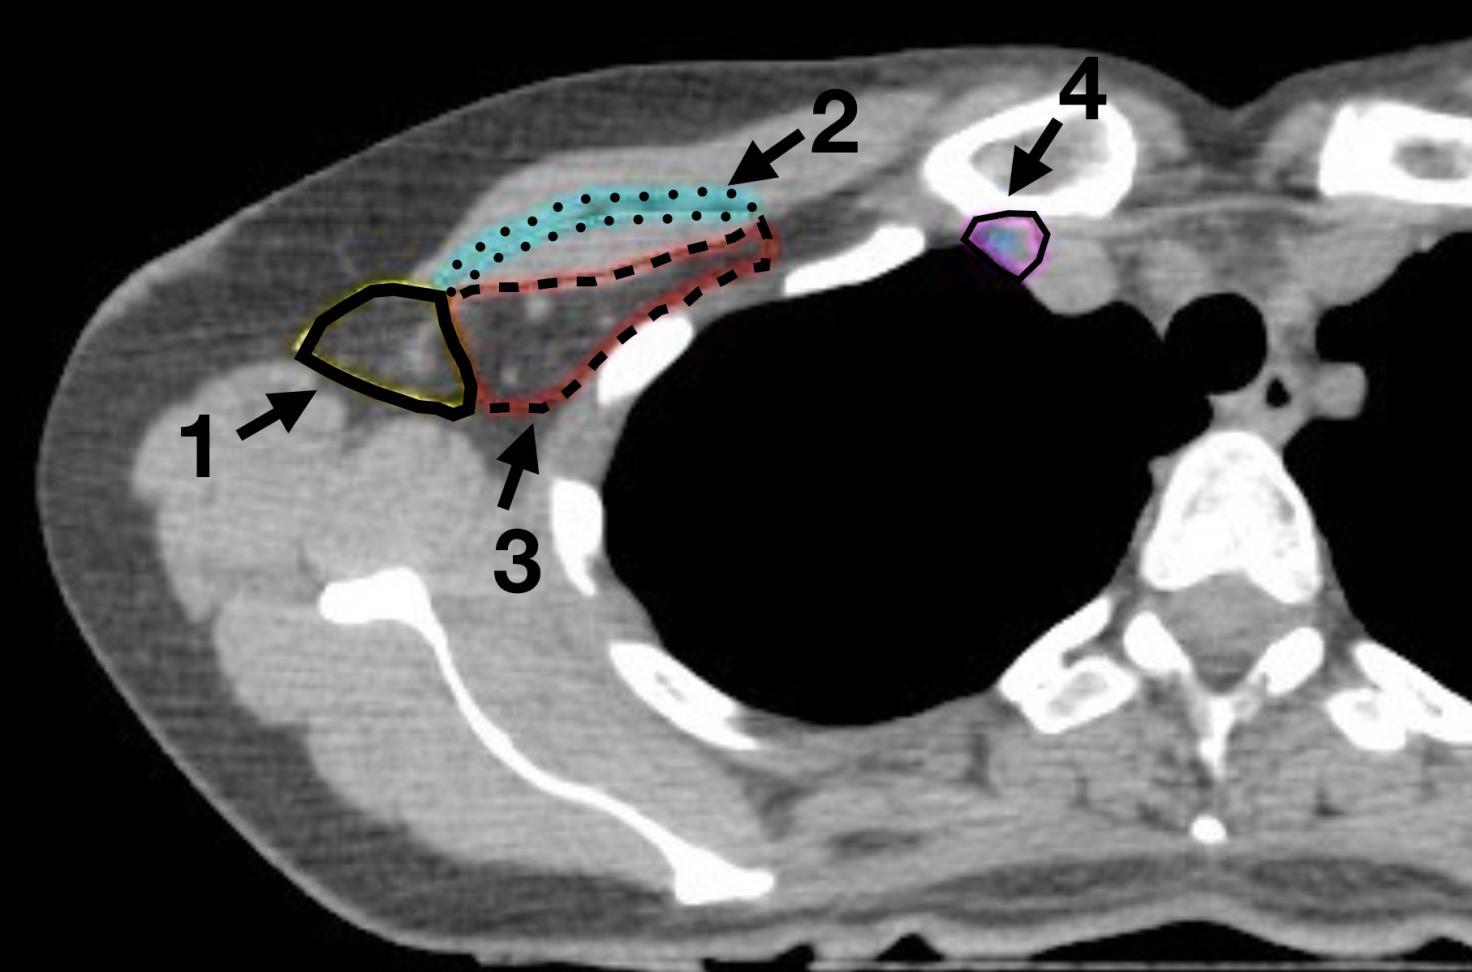

Na rycinie przedstawiono objętości tarczowe używane w uzupełniającym elektywnym napromienianiu chorych na raka piersi. Wskaż prawdziwe stwierdzenie dotyczące objętości tarczowej oznaczonej cyfrą 3: